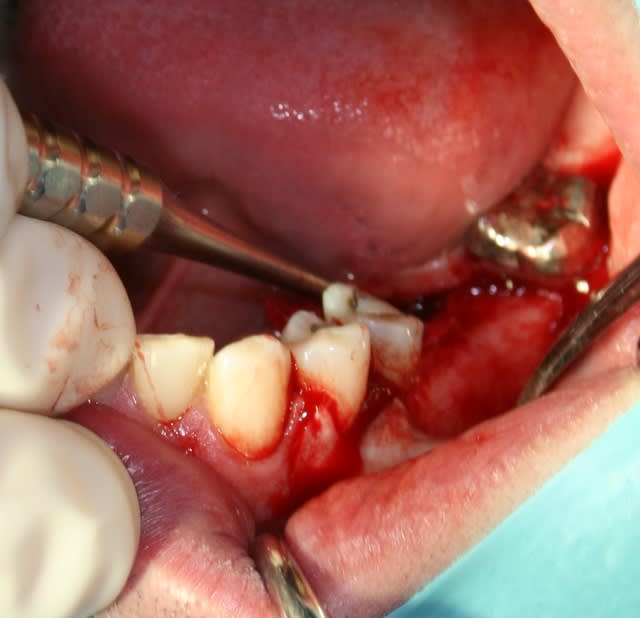

Mise en place de 2 implants IDI Idcam , très bonne impression , forage hypersimplifié ( 4 forets pour du 5.2),et sécurisé grâce aux forets à butée, excellente sensations lors de la mise en place à la clef à cliquet à la position souhaité / à l'os crestal.

personnellement j'aurai fait les implants en derniers (après les soins des autres dents) pour éviter tout risque de contamination et pouvoir réharmoniser le plan d'occlusion

bravo pour ta pose, christophe13, c'est bien propre.